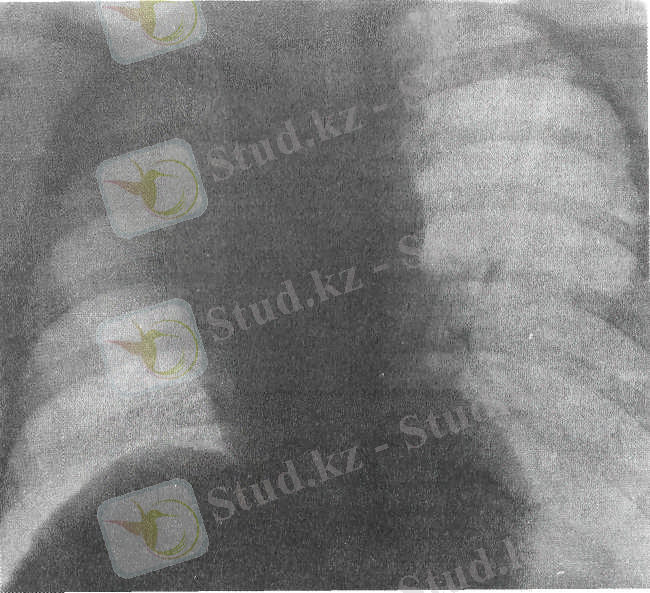

Оң өкпенің ателектазы. Рентгенограмма.

Ателектаздың рентгенологиялық көрінісінде зақымданған сегменттін, бөліктің немесе өкпенің бүкіл көлемі кішірейген, олар біркелкі, қоюлығы жоғары көленке түрінде анықталады. Өкпенің қалған бөліктері және карама-қарсы өкпе, көкірек ортасы ателектаз жаққа қарай ығысады. Тік және бүйірден түсірілген рентгенограммаларда ателектаз көлеңкесі біркелкі, шеттері анық, ал компьютерлі томограммаларда бронхылардың саңылауын көруге болады.